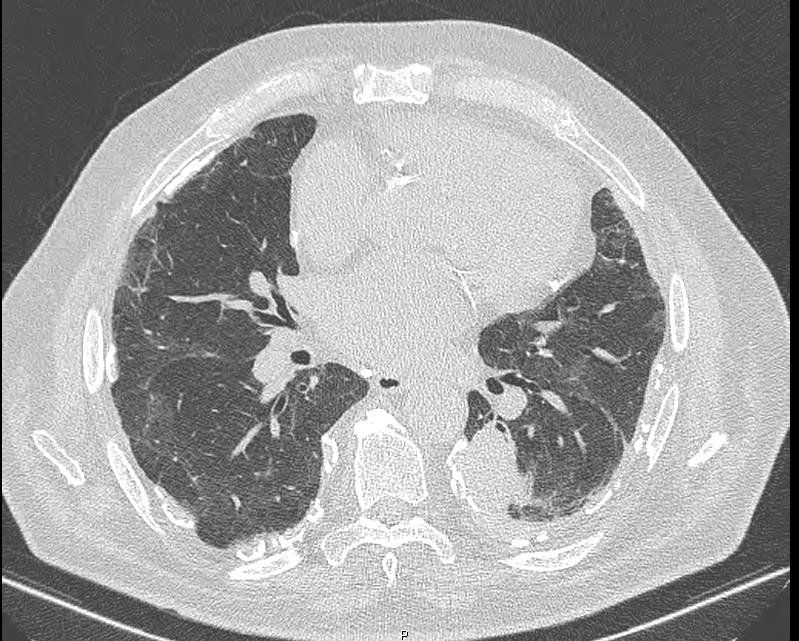

[Caso Clínico] Maio de 2021 - Tórax

Masculino, 76 anos, queixa de dispneia crônica com piora nos últimos 6 meses

Diagnóstico

Pneumoconiose.

Achados de Imagem

- Placas calcificadas pleurais.

- Pneumopatia, podendo ou não estar associada à fibrose pulmonar.

- Atelectasia redonda..